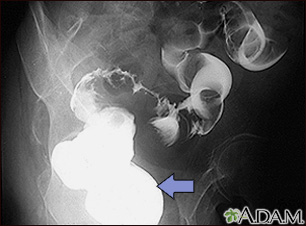

- Confirm findings of another test or x-rays

- Colorectal polyps

- Diverticulosis (abnormal pouches on the lining of the intestines)